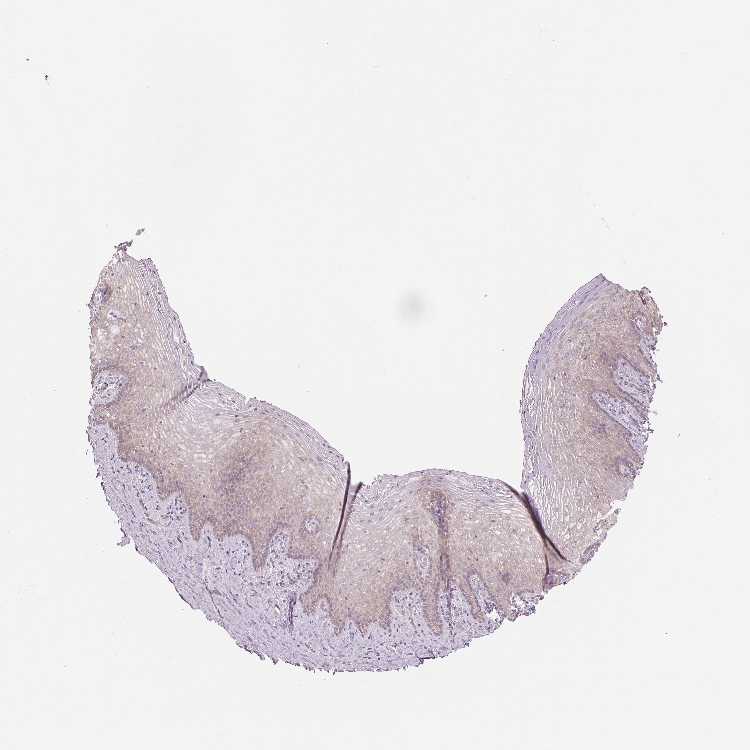

VAGINA - Antibody stainingi

Antibody staining in the annotated cell types in the current human tissue is reported as not detected, low, medium, or high, based on conventional immunohistochemistry profiling in selected tissues. This score is based on the combination of the staining intensity and fraction of stained cells.

Each image is clickable and will lead to virtual microscopy that enables deeper exploration of all samples and also displays staining intensity scores, fraction scores and subcellular localization as well as patient and tissue information for each sample.

Antibody HPA027501

Squamous epithelial cells Low